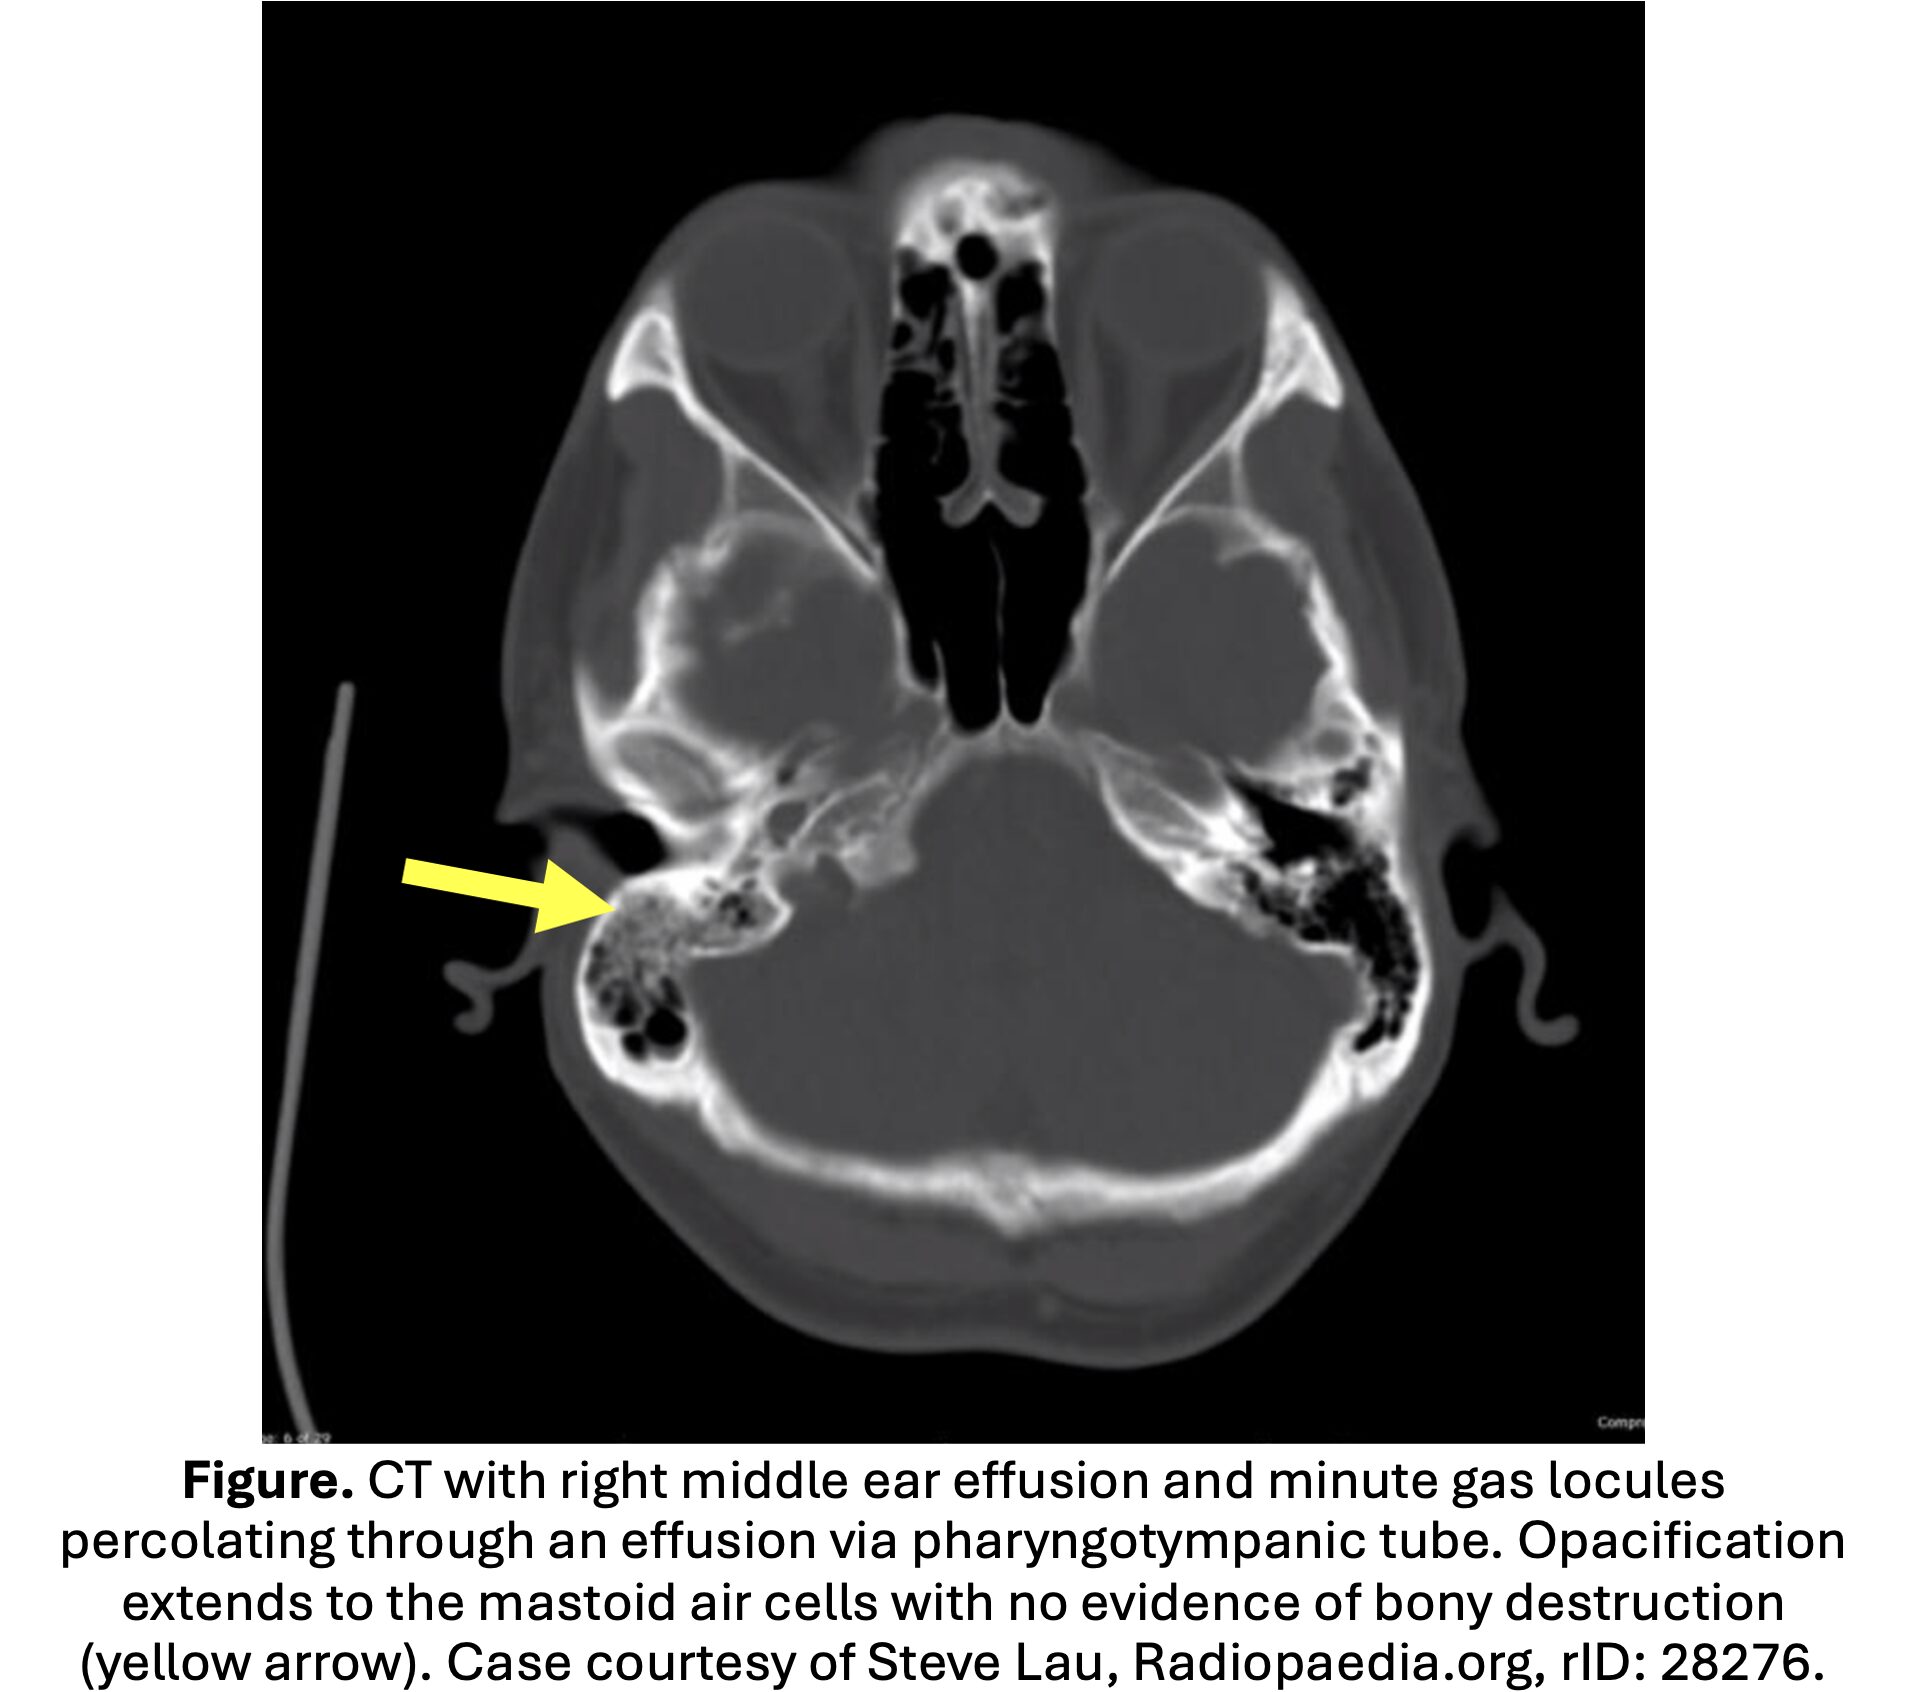

• CT temporal bones with IV contrast modality of choice; sensitivity 87-100% (Antonelli, Bridwell, Vazquez).

• Often demonstrates mastoid opacification or clouding; fluid and mastoid thickening in the mastoid and middle ear is nonspecific and common in pediatric otitis media.

• Diagnostic findings: destruction of the mastoid cortex, periosteal thickening or disruption, and subperiosteal abscess.

• Coalescent mastoiditis: loss of definition in the bony septae defining the mastoid air cells.